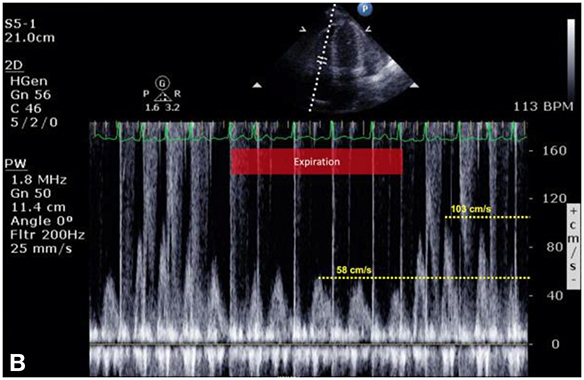

Figure 12.8.: Exaggerated Ventricular Interdependence.

Exaggerated ventricular interdependence. A and B show pulsed-wave Doppler interrogation of transmitral and transtricuspid velocities obtained during a transthoracic echocardiographic study in a patient with suspected cardiac tamponade. The patient is breathing spontaneously; although there is no respirogram on the original images, the patient's marked sinus arrhythmia clearly defines inspiratory and expiratory phases. During negative pressure inspiration, A demonstrates a 25% decrease in transmitral E-wave velocities, whereas B shows a more than 45% increase in transtricuspid E-wave velocities. This exaggerated, reciprocal change in ventricular filling is a hallmark of cardiac tamponade and constrictive physiology. C shows an apical four-chamber view of this patient's heart, demonstrating a large effusion outside the right and left ventricles as well as a deep pool surrounding the right atrium (RA) (labeled by asterisks). Although not evident on this still image, interventricular septal "bounce" was prominent.